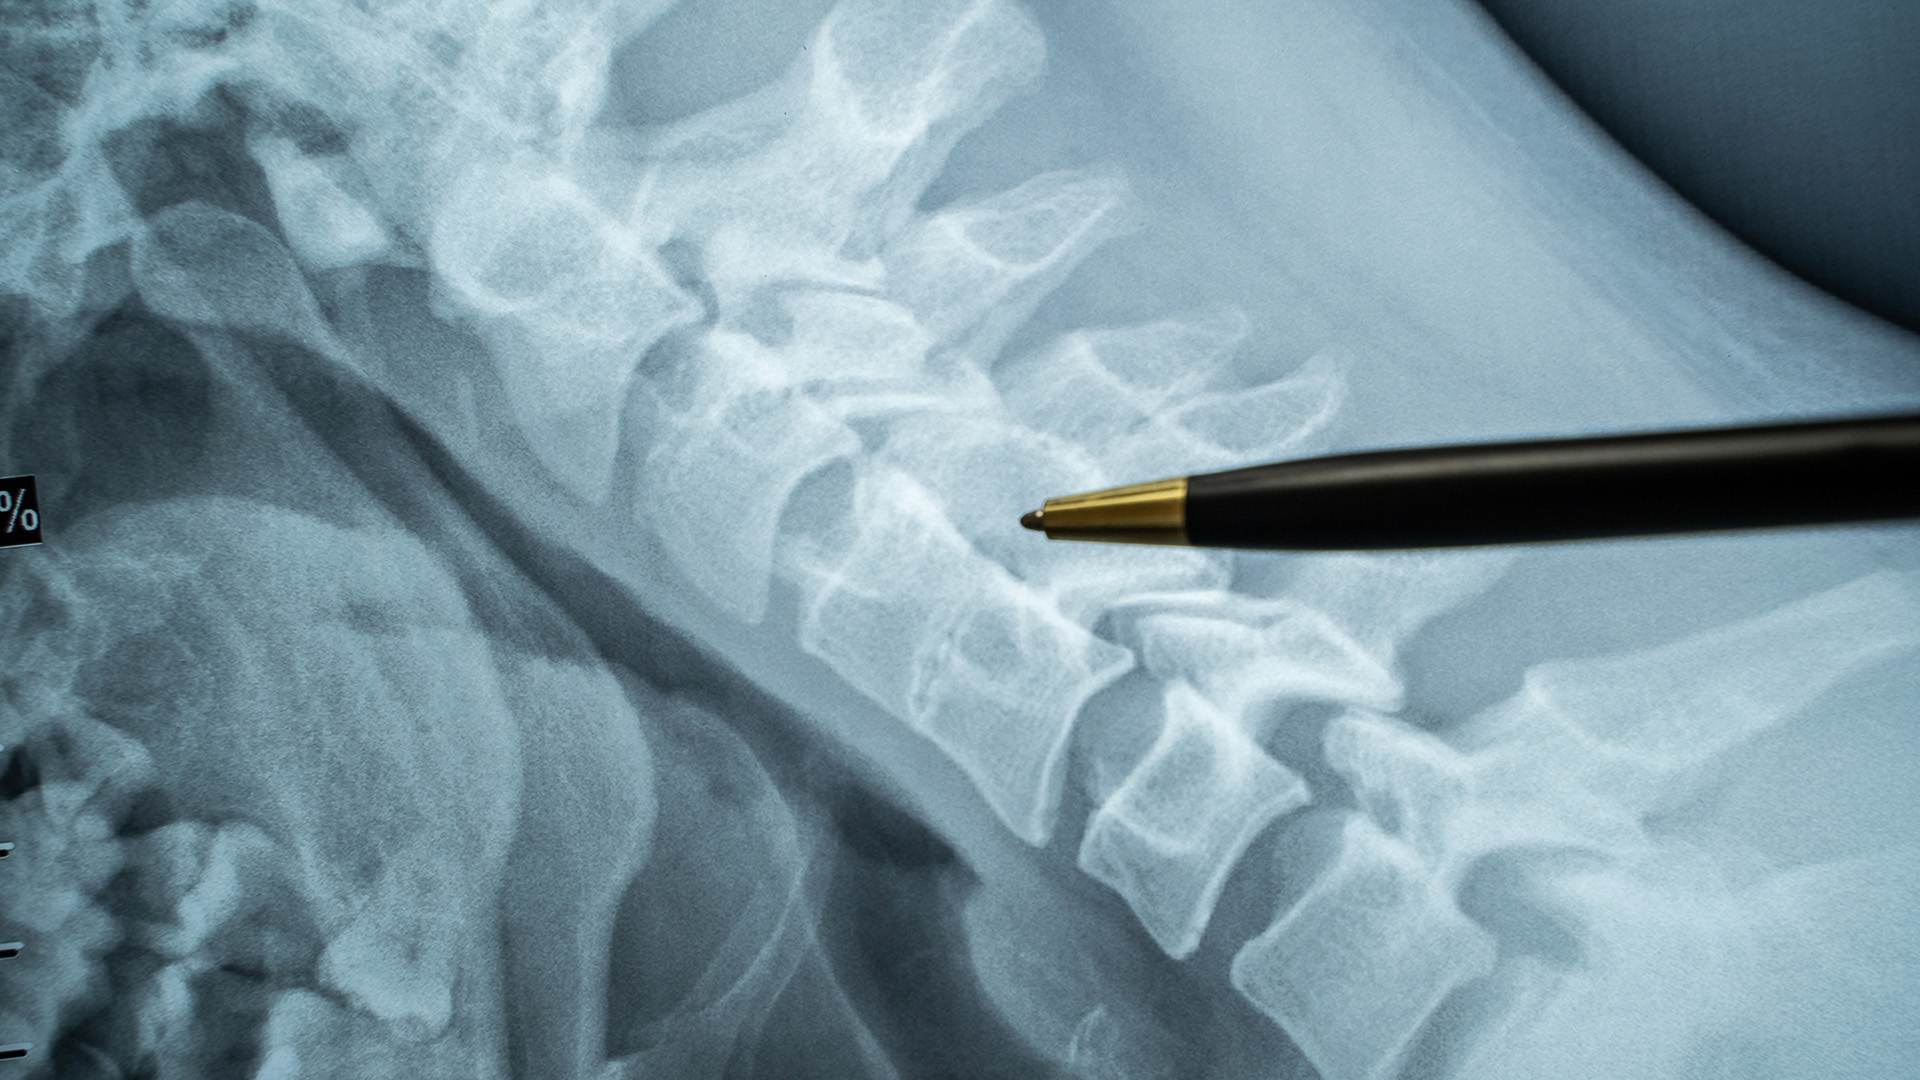

Facet joints are located between the vertebral bones in the spine. They help stabilize the spine and control its movements. Unfortunately, when these joints become inflamed, debilitating neck and back pain can result. Injecting them with an anesthetic and a corticosteroid can often reduce or eliminate suffering caused by many common conditions.